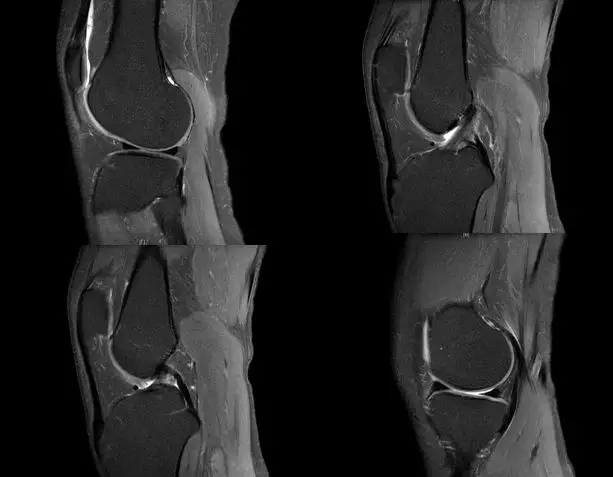

关节扭伤常常导致膝关节相关韧带结构的损伤,如何及时发现这些损伤并进行相关的治疗,是我们临床医师常常面临的问题,除了相关病史、临床体征之外,磁共振扫描也是重要的诊断依据

segond骨折

外髁骨擦伤(Kissing -sign)

陈旧性前交叉韧带断裂